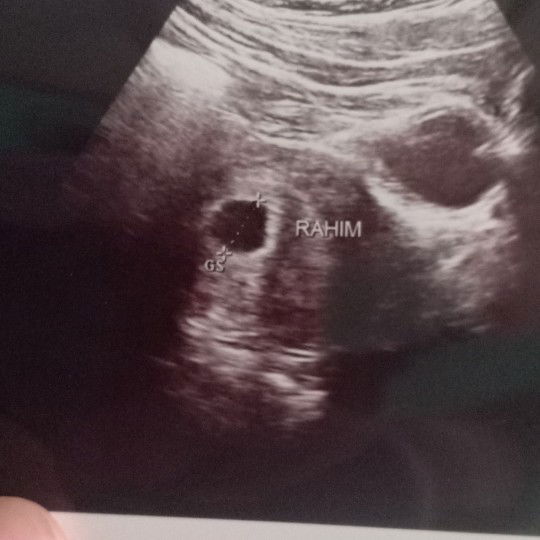

USg 6W

Alkhamdulillah bunda saya langsung k dokter setelah flek tadi mlm,terimakasih atas saran2 dan doanya bunda.dokter bilang Alkhamdulillah sehat walaupun masih blm kelihatan fetalnya karena usia kandungan yg masih 6W,bulan depan suruh cek ulang.